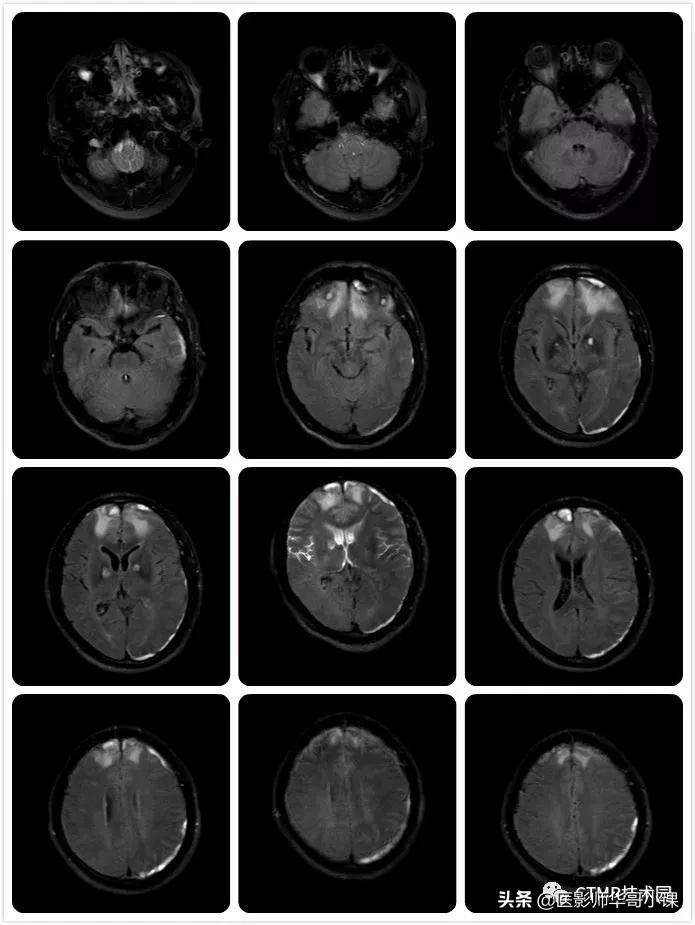

为什么想要去分析这个序列呢,是因为在一次值班中,遇到一个神经外科的病人,颅内有挫裂伤出血,神志有点不清楚,似是可以交流,但还是不配合,检查过程中还是无意识地乱动。听家属和陪同来的护工说,已经来了好几次了,都是因为躁动没做成而回去了。扫了下弥散,看到颅内有好多挫裂伤出血灶。遇到这样的病人,我通常都用机器自带的单次激发序列来试试,其中就有一个序列就是 SSh_FLAIR,用来扫压水。那么扫的效果怎么样呢?(总共18层 6mm/1mm,只显示部分)

由于这个病人一个劲乱动,还时不时地抬头,我们可以看到,扫出的图像感觉不是很连续,或者说相邻两幅图像之间有重复的部分。还可以看到第三行第二列的图像有部分脑脊液没有被抑制完全,而且可以看到前后两图比起来它的位置有所变化,即病人抬头了: